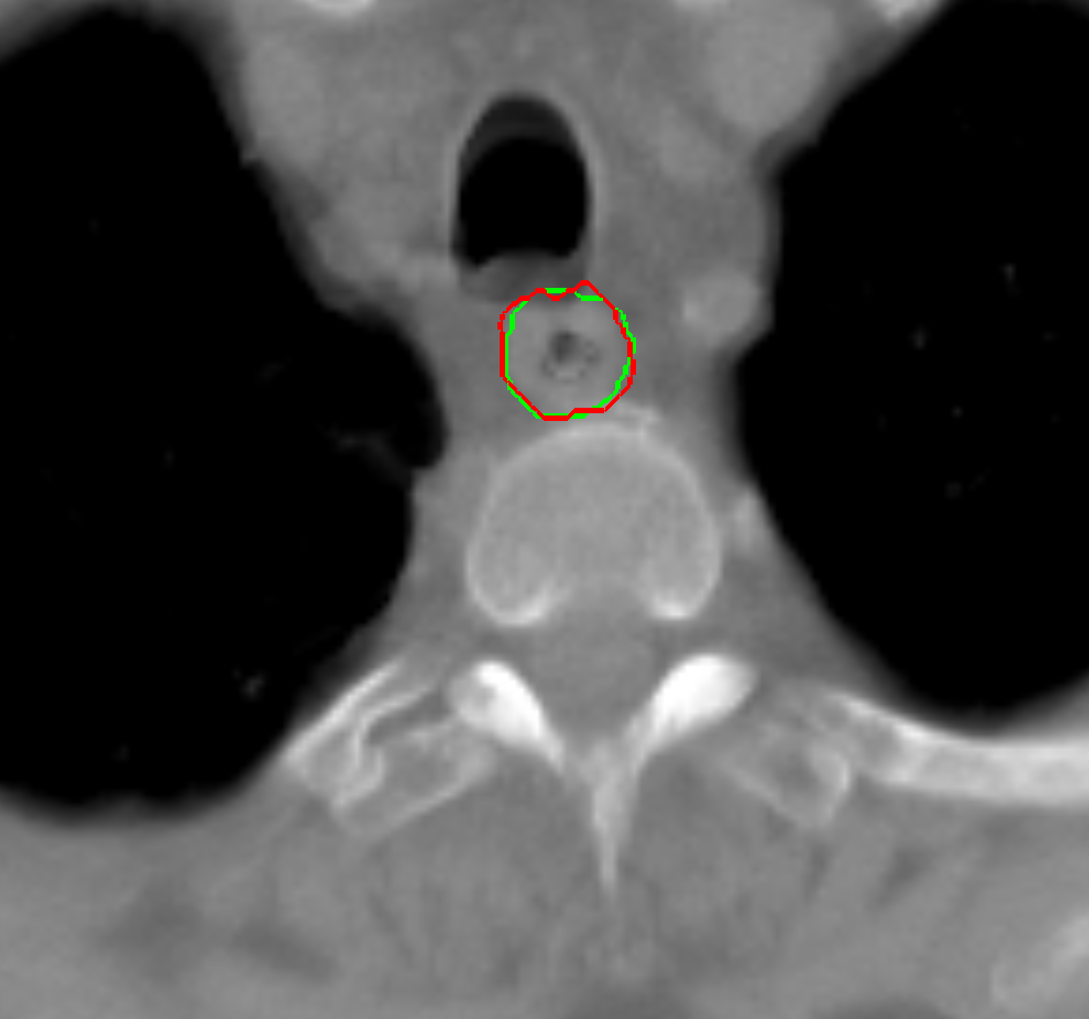

Visual results of our algorithm compared to the reference contour for 6 cases in axial and sagittal view are depicted in Fig. 5. From the sagittal views it can be observed that manual contours are not as smooth as the automatic contours, which could be due to the breathing artifacts. The use of convolutions and post-processing in 3D aids at processing information of the 3D context through several slices, which is reflected in the smoother automatic contours shown in these images. On the other hand, from the axial views we can realize that, despite of the similarity with respect to neighboring tissues, and heterogeneity of the inner region of the esophagus, our automatic system provides contours that are comparable with the reference standard.

Refer to caption a) clinical case 09 sagittal view Refer to caption b) clinical case 13 sagittal view Refer to caption c) clinical case 20 sagittal view

Refer to caption d) clinical case 09 axial view Refer to caption e) clinical case 13 axial view Refer to caption f) clinical case 20 axial view

Refer to caption g) public case 01 sagittal view Refer to caption h) public case 12 sagittal view Refer to caption i) public case 24 sagittal view

Refer to caption j) public case 01 axial view Refer to caption k) public case 12 axial view Refer to caption l) public case 24 axial view

Figure 5: Contouring results for 6 cases in different views. The green line indicates the reference standard, the red line depicts the contour generated by the proposed algorithm.